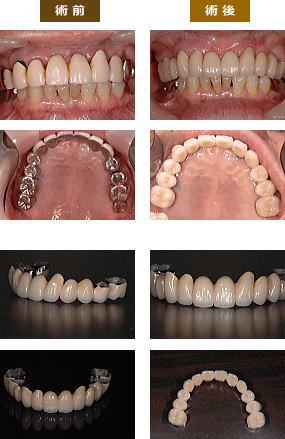

(左右の側切歯が矮小歯で正中離開があり)

MTM(小矯正)を行いポーセレン・ラミネートベニアを左右の側切歯に施行し審美性を回復。

ホワイトニングとメタルボンドで審美性回復。

ホワイトニングとメタルボンドで審美性回復。

メタルボンドで審美性回復。

メタルボンドブリッジを作って審美性回復。

右上にインプラント、左下にインプラントを施行し咬み合わせを回復し、上の前歯にオールセラミックを作って咬み合わせと審美性を回復。

不適メタルボンドをオールセラミックに変えて審美性を回復。

不適メタルボンドをやり変えて審美性回復。

上の歯が7本欠損しており、歯周病もあるのでメタルボンドのフルブリッジで咬み合せを安定させました。

左上2番の前歯がハセツしており、左上前に2本インプラントを入れ。骨増生と、歯肉移植を行い歯肉の厚みを確保し、メタルボンドを入れました。